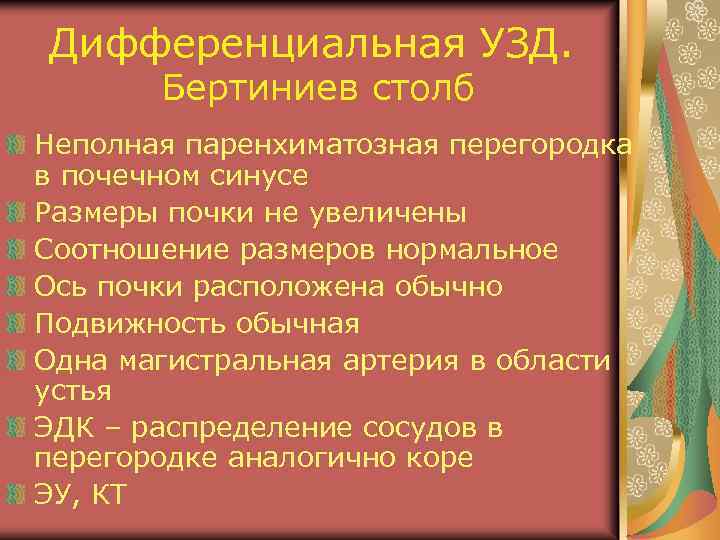

Дифференциальная УЗД. Бертиниев столб Неполная паренхиматозная перегородка в почечном синусе Размеры почки не увеличены Соотношение размеров нормальное Ось почки расположена обычно Подвижность обычная Одна магистральная артерия в области устья ЭДК – распределение сосудов в перегородке аналогично коре ЭУ, КТ